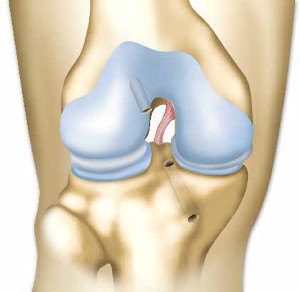

Ο πρόσθιος χιαστός σύνδεσμος του γόνατος έχει φθαρεί εξαιτίας ενός τραυματισμού.

Αυτός ο σύνδεσμος όταν είναι ακέραιος εμποδίζει την πρόσθια μετακίνηση της κνήμης κατά την εκτέλεση συγκεκριμένων κινήσεων.

Δεν είναι ωστόσο ο μόνος, που εμποδίζει τις μετατοπίσεις της κνήμης. Οι μύες, η επιγονατίδα και οι τένοντες του γόνατος συμβάλλουν επίσης στη σταθερότητα της άρθρωσης. Ο πρόσθιος χιαστός σύνδεσμος μπορεί να υποστεί ολική ή μερική ρήξη.

Εάν ο τραυματισμός είναι σοβαρός, μπορεί να συμβεί πρόσθια μετατόπιση της κνήμης κατά το περπάτημα.